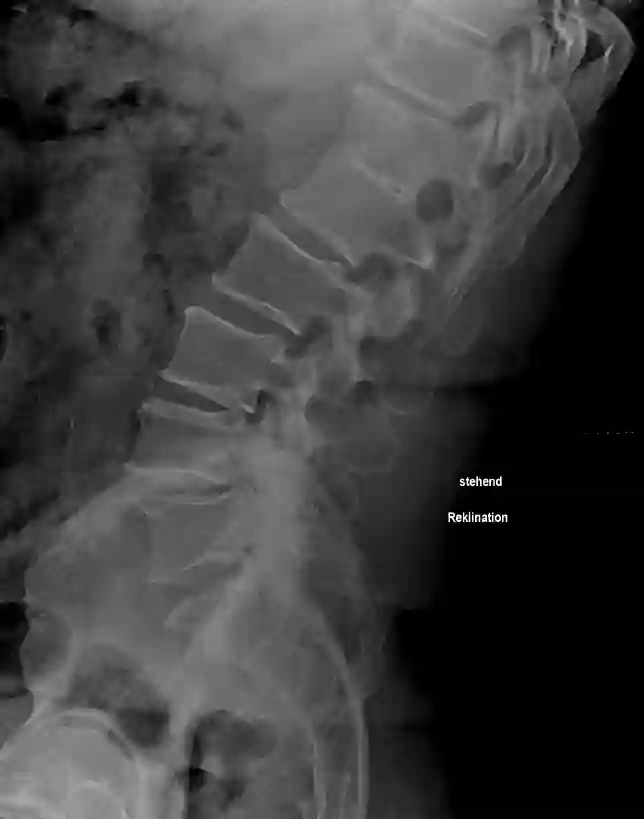

Reklination LWS

Seitliche Röntgenaufnahme einer reklinierten Lendenwirbelsäule.